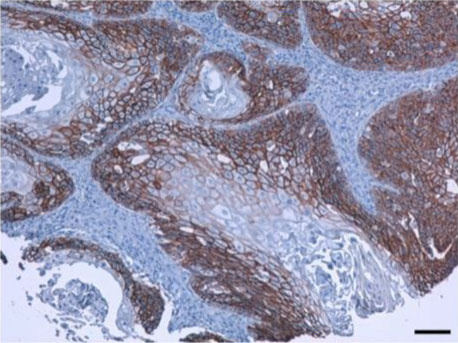

免疫組織染色

スケールバー : 100 μm

- 動物種

- ヒト

- 組織

- 口腔扁平上皮がん (OSCC)

- 抗体濃度

- 1 μg/mL